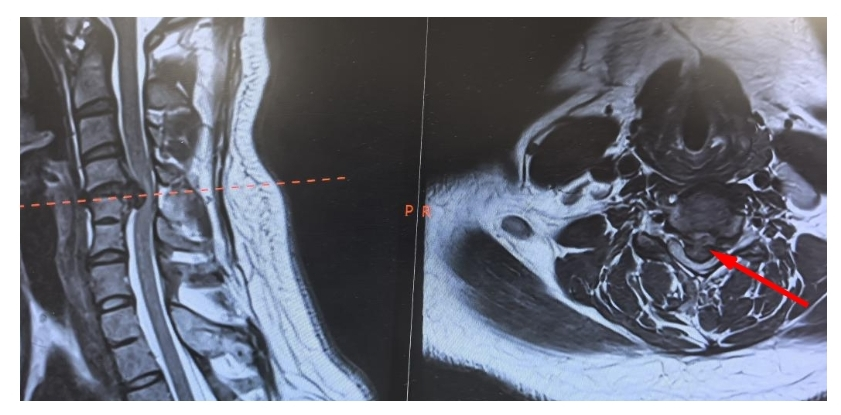

术前颈椎MR

王彪结合病史及检查结果,颈椎间盘突出症诊断明确,且脱出髓核占到椎管的80%以上,属于巨大型椎间盘脱出,颈部脊髓严重受压。这是近几年临床比较少见的一例高风险颈椎手术,术中稍有不慎,就可能出现脊髓损伤导致瘫痪。巨大的风险让很多医院的医生望而却步。